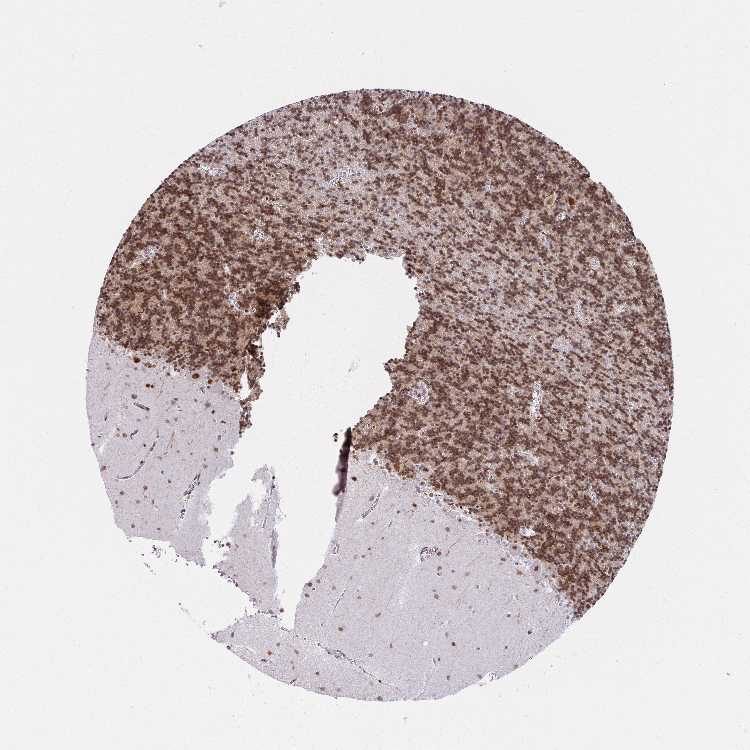

BRAIN CEREBELLUM Show tissue menu

CEREBELLUM - Expression summary

CEREBELLUM - Antibody stainingi

Antibody staining in the annotated cell types in the current human tissue is reported as not detected, low, medium, or high, based on conventional immunohistochemistry profiling in selected tissues. This score is based on the combination of the staining intensity and fraction of stained cells.

Each image is clickable and will lead to virtual microscopy that enables deeper exploration of all samples and also displays staining intensity scores, fraction scores and subcellular localization as well as patient and tissue information for each sample.

Antibody HPA055861Antibody CAB004212

Purkinje cells HighNot detected

Cells in granular layer HighHigh

Cells in molecular layer HighMedium